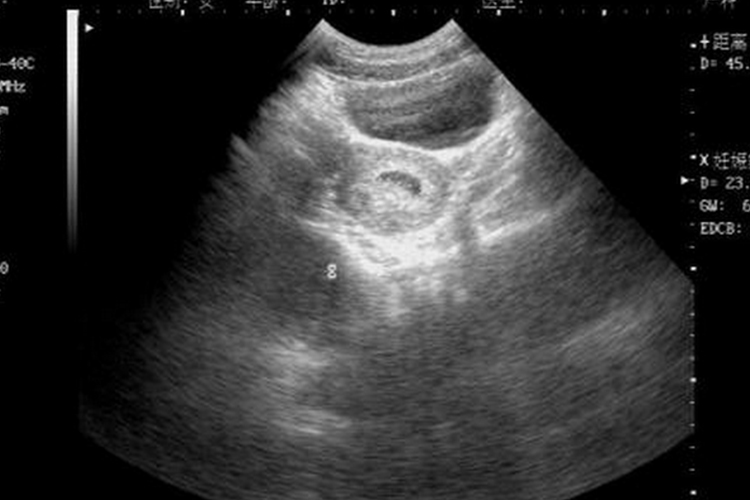

怀孕5周时间较短,胎儿尚未成型,宫腔内为圆形或椭圆形的妊娠囊。

怀孕5周时,孕妇宫腔内存在圆形或卵圆形的妊娠囊,胎儿尚未成型,可通过B超观察到。此外孕妇还会出现停经、尿频、乳房胀痛、阴道黏膜和宫颈阴道部充血呈蓝紫色,以及畏寒、头晕、流涎、乏力嗜睡、食欲缺乏、喜食酸物、厌恶油腻、恶心、晨起呕吐等早孕反应。